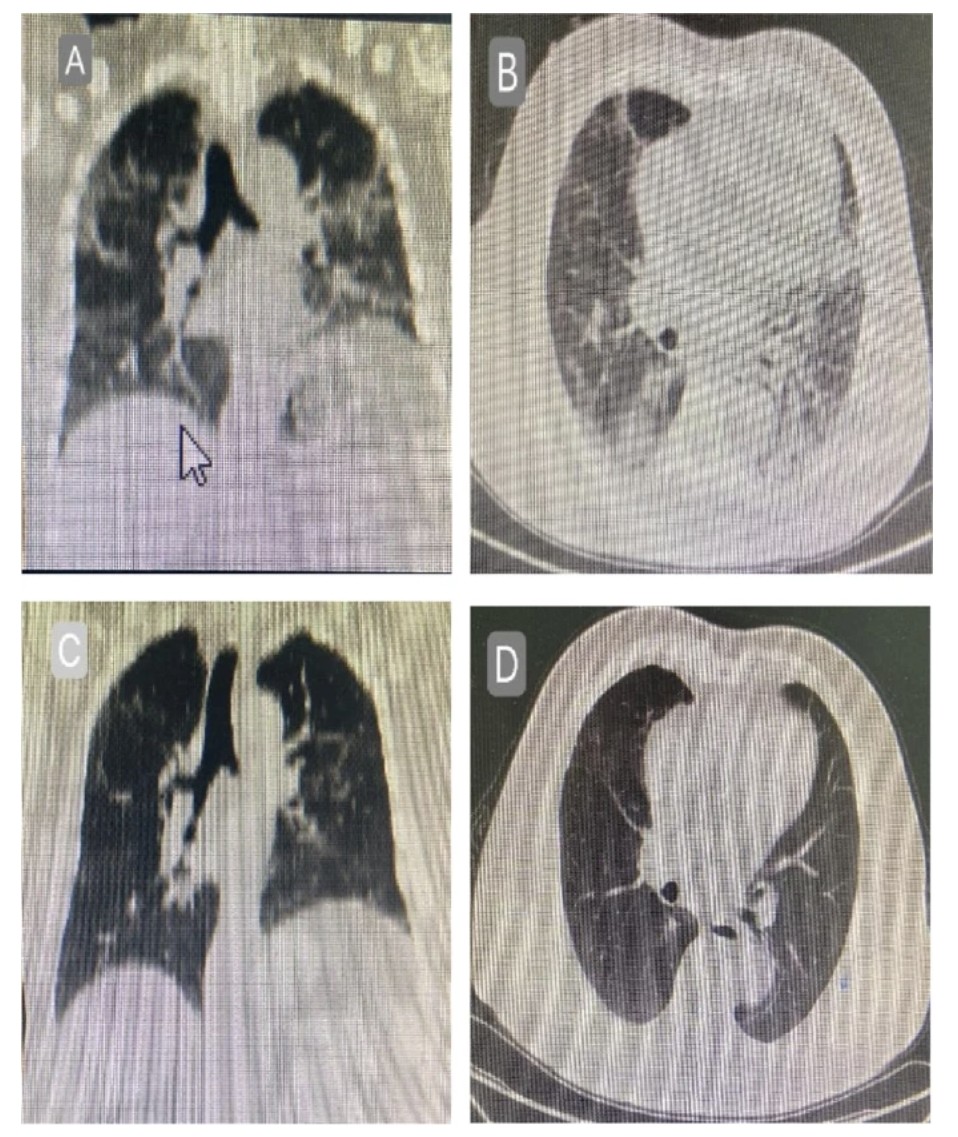

๐—–๐—ข๐—ฅ๐—ง๐—œ๐—–๐—ข๐—ฆ๐—ง๐—˜๐—ฅ๐—ข๐—œ๐——๐—ฆ ๐—ฎ๐—ป๐—ฑ ๐—–๐—ข๐—ฉ๐—œ๐——-19

(2 ๐˜ฏ๐˜ฆ๐˜ธ ๐˜ด๐˜ต๐˜ถ๐˜ฅ๐˜ช๐˜ฆ๐˜ด)

3) 1st study :

"Efficacy of different doses of corticosteroids in treating severe COVID-19 pneumonia"

virologyj.biomedcentral.com/articles/10.11โ€ฆ

Image